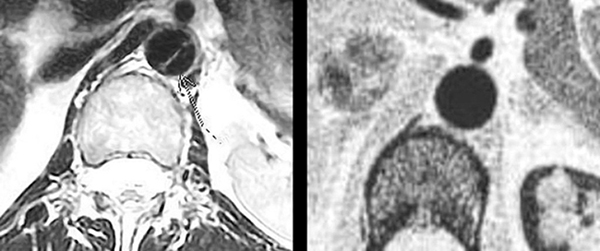

Трис Гриффин обратилась к врачу в начале 2013 года из-за боли в пояснице, которая, как она опасалась, могла быть рецидивом её борьбы с раком. Томография показала “расслоение аорты” в её сердце, что побудило врачей провести дальнейшие тесты и наметить неотложную операцию на следующий день. На фото ясно видна линия, которая проходит через сердце – очевидно, что это трещина, которая означала бы быструю и почти неминуемую смерть в случае разрыва.

На следующий день, после того, как верующие помолились за неё, врачи провели ещё одну компьютерную томографию, чтобы точно определить местоположение трещины перед операцией. На этот раз снимки показали абсолютно здоровое сердце. Весьма озадаченный, хирург сказал миссис Гриффин: “Я не знаю, что вам сказать. У вас было расслоение аорты, но теперь от этого не осталось и следа”. Он показал ей снимки сделанные до и после молитвы. “Вы можете идти. И между прочим, у вас также нет никакого рака. Вы абсолютно здоровы”.

Стрелка, нанесённая врачом, указывает на аорту, которая представляет собой темную, круглую областью в центре изображения. Диагональная линия – это аневризм или расслоение аорты, которая нуждается в срочной операции и может оказаться фатальной в случае разрыва. На следующий день был осуществлено второе сканирование сердца. Расслоение полностью исчезло и никогда больше не возникало.